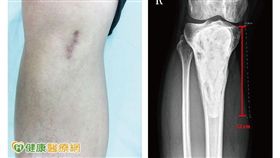

腳踝腫痛莫輕忽 恐因罕見骨腫瘤惹禍

20幾歲年輕人通常是體力最好的時候,相約打球、瘋路跑...